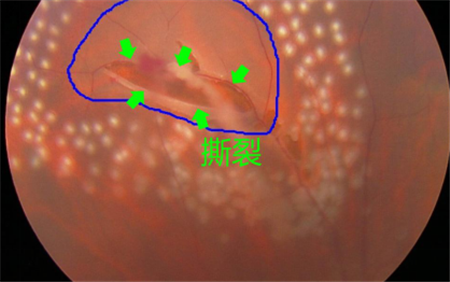

視網(wǎng)膜退化以及撕裂、后玻璃體脫落、葡萄膜炎、糖尿病或者黃斑變性引起的眼底出血等,可導(dǎo)致飛蚊癥產(chǎn)生,這種情況就屬于惡性飛蚊。雖然飛蚊本身并不會導(dǎo)致眼睛失明,但這些原發(fā)疾病若不及時(shí)治療,失明的風(fēng)險(xiǎn)卻是非常大的。

所以在出現(xiàn)飛蚊癥時(shí),建議上醫(yī)院做個(gè)檢查,看看屬于哪一種飛蚊。尤其是突然出現(xiàn)大量飛蚊、閃光,并伴隨視力下降或者視野缺損的情況,更需要及時(shí)就醫(yī)。在上海眼科醫(yī)院排名治療惡性飛蚊需要結(jié)合患者的原發(fā)疾病進(jìn)行治療,比如由視網(wǎng)膜裂孔導(dǎo)致的飛蚊癥,需要通過激光治療將裂孔封閉,從而避免視網(wǎng)膜進(jìn)一步脫落。